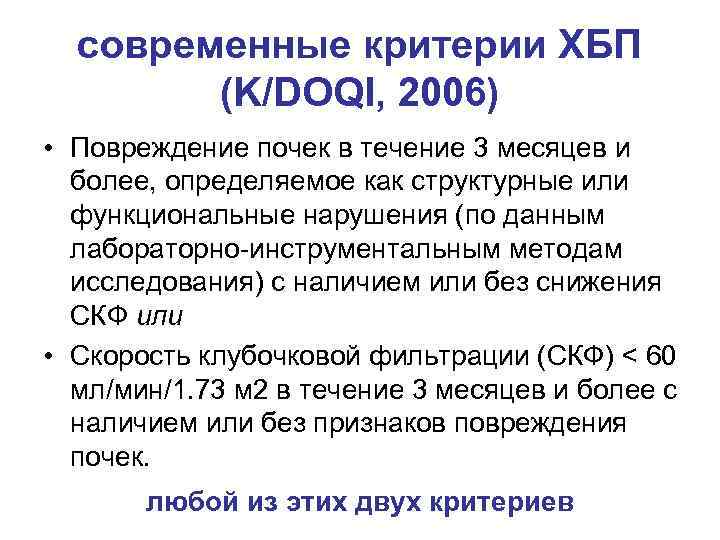

современные критерии ХБП (K/DOQI, 2006) • Повреждение почек в течение 3 месяцев и более, определяемое как структурные или функциональные нарушения (по данным лабораторно-инструментальным методам исследования) с наличием или без снижения СКФ или • Скорость клубочковой фильтрации (СКФ) < 60 мл/мин/1. 73 м 2 в течение 3 месяцев и более с наличием или без признаков повреждения почек. любой из этих двух критериев

современные критерии ХБП (K/DOQI, 2006) • Повреждение почек в течение 3 месяцев и более, определяемое как структурные или функциональные нарушения (по данным лабораторно-инструментальным методам исследования) с наличием или без снижения СКФ или • Скорость клубочковой фильтрации (СКФ) < 60 мл/мин/1. 73 м 2 в течение 3 месяцев и более с наличием или без признаков повреждения почек. любой из этих двух критериев

Значение СКФ < 60 мл/мин. (для диагностики ХБП) выбрано ввиду соответствия гибели более 50% нефронов. • Если признаков повреждения почек нет, а СКФ находится в диапазоне 60 -89 мл/мин. , то стадия ХБП не устанавливается. Данное состояние оценивается как снижение СКФ, что обязательно отражается в диагнозе. • У пожилых лиц (60 лет и старше) показатели СКФ в пределах 60– 89 мл/мин без инициирующих факторов риска ХБП расцениваются как возрастная норма.

Значение СКФ < 60 мл/мин. (для диагностики ХБП) выбрано ввиду соответствия гибели более 50% нефронов. • Если признаков повреждения почек нет, а СКФ находится в диапазоне 60 -89 мл/мин. , то стадия ХБП не устанавливается. Данное состояние оценивается как снижение СКФ, что обязательно отражается в диагнозе. • У пожилых лиц (60 лет и старше) показатели СКФ в пределах 60– 89 мл/мин без инициирующих факторов риска ХБП расцениваются как возрастная норма.